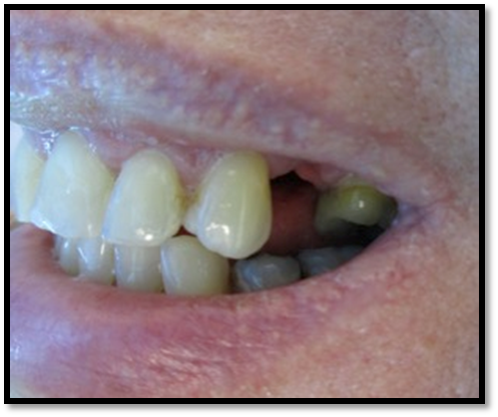

Resident Case Photos

The following are before and after photos of dental patients who have been treated by the residents at NYC Health + Hospitals/South Brooklyn Health. To apply to the program visit the Dental GPR Page and click on Application Information.

Full Crowns